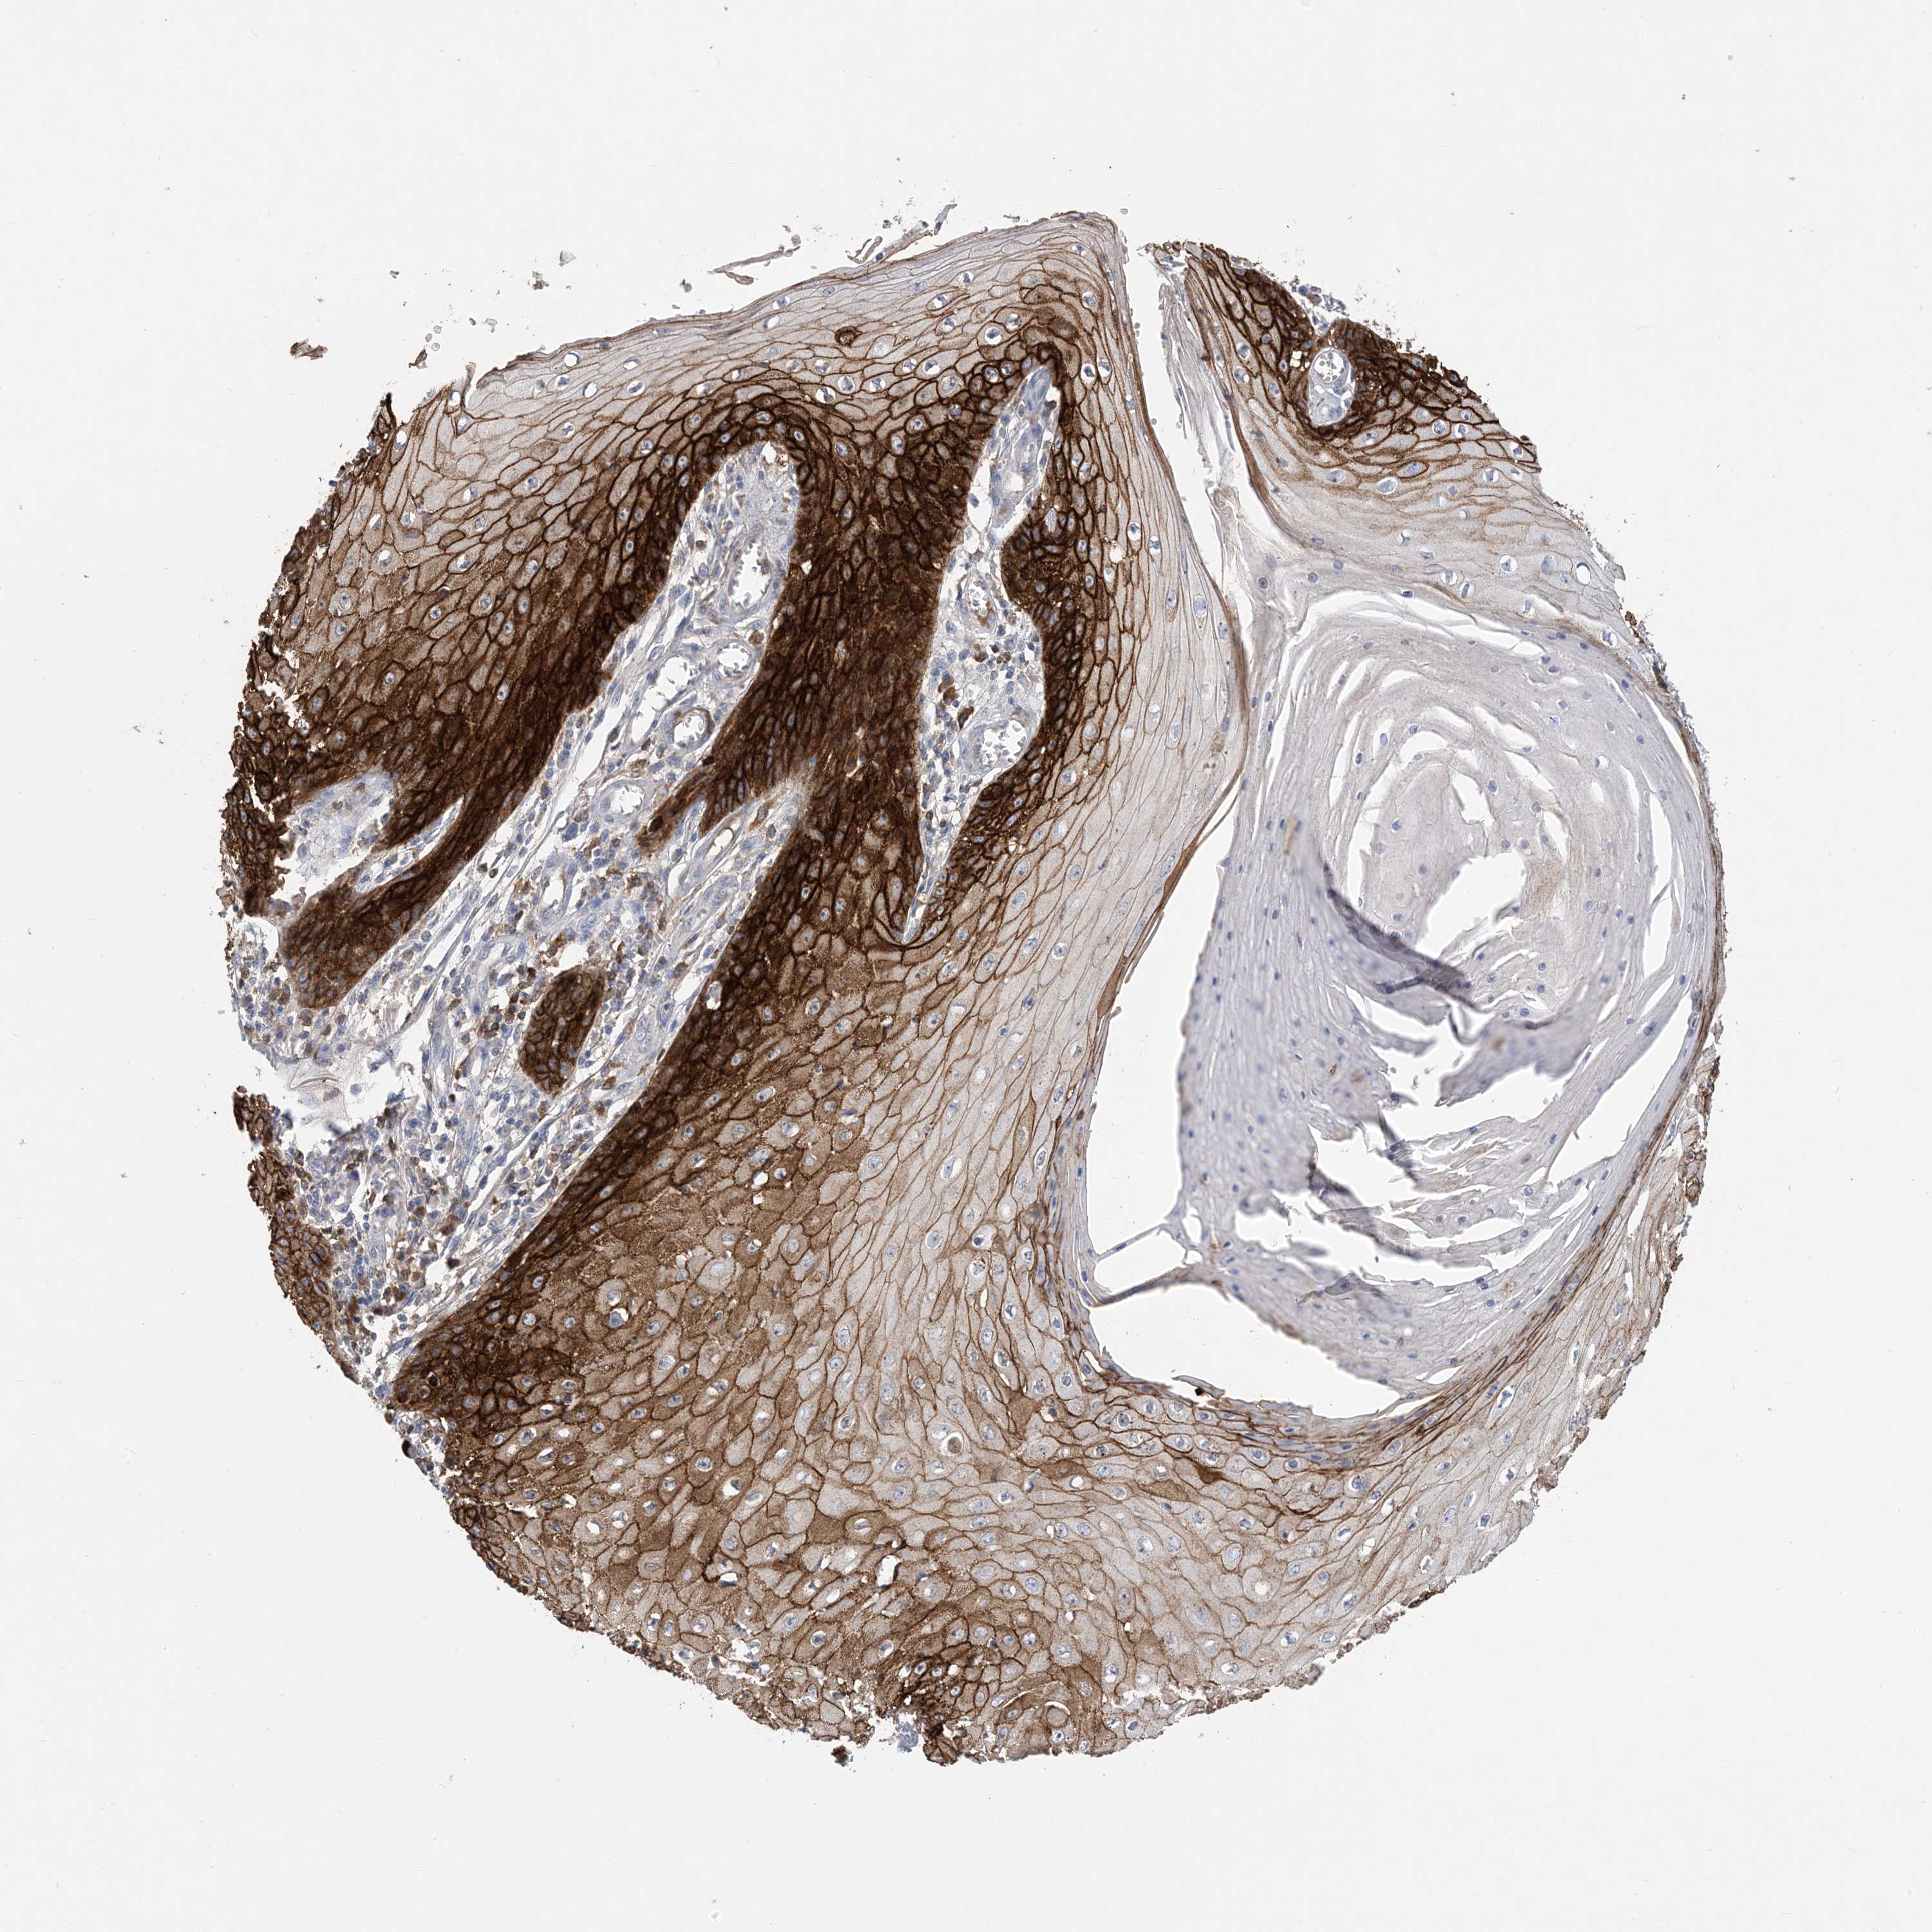

Basal cell and squamous cell cancer

SKIN CANCER - Protein expressioni

A mouse-over function shows sample information and annotation data. Click on an image to view it in a full screen mode. Samples can be filtered based on level of antibody staining by selecting one or several of the following categories: high, medium, low and not detected. The assay and annotation is described here.

Antibody stainingi

Antibody staining in the annotated cell types in the current human tissue is reported as not detected, low, medium, or high, based on conventional immunohistochemistry profiling in selected tissues. This score is based on the combination of the staining intensity and fraction of stained cells.

Each image is clickable and will lead to virtual microscopy that enables deeper exploration of all samples and also displays staining intensity scores, fraction scores and subcellular localization as well as patient and tissue information for each sample.

Antibody HPA049265

Antibody CAB037328

Staining

High

Medium

Low

Not detected

Intensity

Strong

Moderate

Weak

Negative

Quantity

>75%

75%-25%

<25%

None

Location

Nuclear

Cytoplasmic/membranous

Cytoplasmic/membranous,nuclear

Squamous cell carcinoma, metastatic, NOS